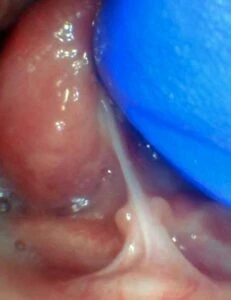

IMAGES OF TONGUE- AND LIP-TIES

Spectrum of lip restriction in a child

Spectrum of tongue restriction in a child

Posterior tongue-tie in a child seen with lifting the tongue. The posterior or “hidden”tongue-tie can cause the same symptoms including nursing pain and poor weight gain, as a to-the-tip tie in a child